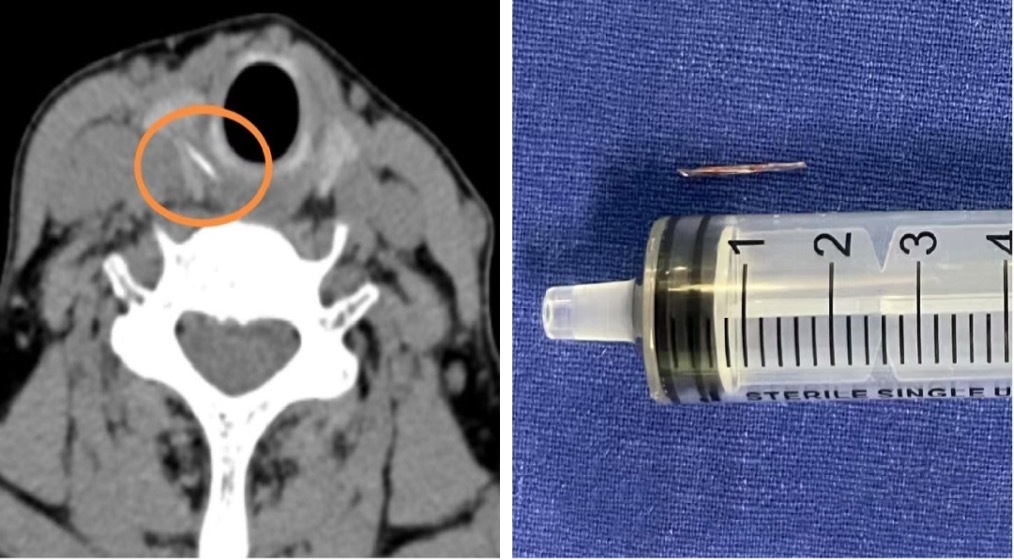

医生从患者右侧甲状腺中,取出了一枚长约1.5厘米的鱼刺。上海市第十人民医院 供图

意识到问题的严重性,李阿姨最终决定做CT,影像结果证实了之前的猜测:在右侧甲状腺位置,发现了一条索状的高密度异物影,这极有可能是鱼刺穿透食道壁,扎进了甲状腺。这种情况比较复杂,仅依靠内窥镜做微创手术,无法取出这根‘逃逸’的鱼刺,经过审慎评估,医疗团队决定为李阿姨实施全麻下颈侧切开术。

手术中,医生小心翼翼地探入患者颈部,精细地分离组织,完好地保护其甲状腺、甲状旁腺以及喉返神经,最终成功从患者右侧甲状腺中取出了一枚长约1.5厘米的鱼刺。探查还发现,患者周围的食道黏膜有轻度肿胀,遂对创面作了消毒处理。术后,李阿姨喉咙疼痛明显减轻,经过抗炎治疗,颈部的切口愈合良好。